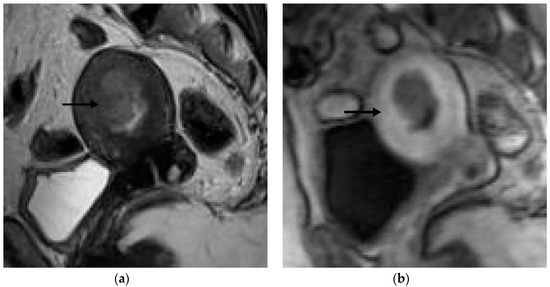

Figure 1, Figure 2, Figure 3 and Figure 4 depict the representative MRI images of tumors with < 50% myometrial invasion and ≥50% myometrial invasion, as well as the representative combined T2WI+DCE-MRI images for false-positive and false-negative cases, respectively. The diagnostic performance of MRI in predicting the depth of myometrial invasion is presented in Table 2 and Table 3. The depth of myometrial invasion (any depth) was correctly determined in 75% (n = 24) and 78% (n = 25) of cases on T2WI and DCE-MRI alone, respectively, whereas the percentage increased to 91% (n = 29) of cases when the T2W images were read together with those obtained by DCE-MRI.

Figure 1. Representative MRI images of endometrial carcinoma with <50% myometrial invasion. (a) Axial T2WI, (b) sagittal T2WI, and (c) sagittal DCE-MRI images during the early acquisition stage. Tumors (arrow) with <50% myometrial invasion presented as iso- to mildly hyperintense on T2WI compared to the myometrium (a,b) with an intact junctional zone. On DCE-MRI, the tumors appeared as hypointense masses compared to the adjacent myometrium with intact subendometrial enhancement (SEE), indicating a tumor that is confined to the endometrium (c). Abbreviations: MRI, magnetic resonance imaging; dynamic contrast-enhanced magnetic resonance imaging (DCE-MRI); T2WI, T2-weighted imaging.